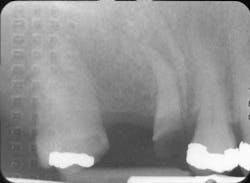

Last month we asked you to diagnose the X-ray below and send in your answers on what you think the operator may have done wrong. Today we provide you with the image’s diagnosis!Congratulations to Beckie Wooters from Northwestern Michigan College in Traverse City, Mich., for correctly diagnosing last month’s image. Beckie will be awarded a $25 gift card. Be sure to send in your diagnosis for this month’s Diagnose the X-Ray for a chance to win.

Lead foil image — caused by packet placed backwards (non-tube side) during patient exposureX-Ray answersPacket exposed backwards Intraoral films exhibiting an unexpected lighter density along with a “lead-foil pattern” are usually the result of the packet being incorrectly placed in a patient’s mouth backwards or exposed to the non-tube side.Kodak packet lead foils are designed with a raised knurl pattern. If a packet is positioned backwards and exposed, the knurl pattern can be used as a tool to inform an operator of a placement error. When this error occurs, intraoral films are typically lighter in density and lower in contrast, due to reduced exposure of the film.Some manufacturers of intraoral dental packets have no pattern on the lead foils, making the connection to a placemat error more difficult. All Kodak intraoral packets also emboss “Opposite Side Tube Side” as a tool for proper packet positioning. Tips and TricksUnderexposed radiograph with special or continuous patternProblem: Underexposed radiograph with a raised diamond or herringbone patternPossible cause: Film packet positioned backwards and exposed through the back side (non-tube side) of the packetHow to correct: Establish a protocol to prevent packets from being positioned backwards in a patient’s mouth.Hints: Positioning guides on a Kodak packet